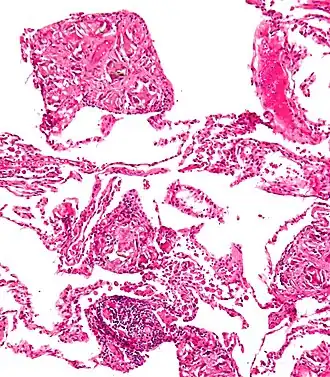

La talcosi è una pneumoconiosi causata dalla prolungata inalazione di polveri di talco.

È una malattia professionale che può colpire gli addetti all'industria della ceramica, dei coloranti, della carta e della porcellana in cui viene utilizzata la sostanza, anche se si ritiene che i responsabili siano più che altro i contaminanti come il quarzo o l'asbesto, essendo il talco puro inerte[1].

La malattia è inoltre correlata all'uso di eroina, nella quale il talco può essere utilizzato come adulterante per incrementarne il peso e il valore di mercato[2]. È uno dei molti rischi associati all'uso di eroina[3].